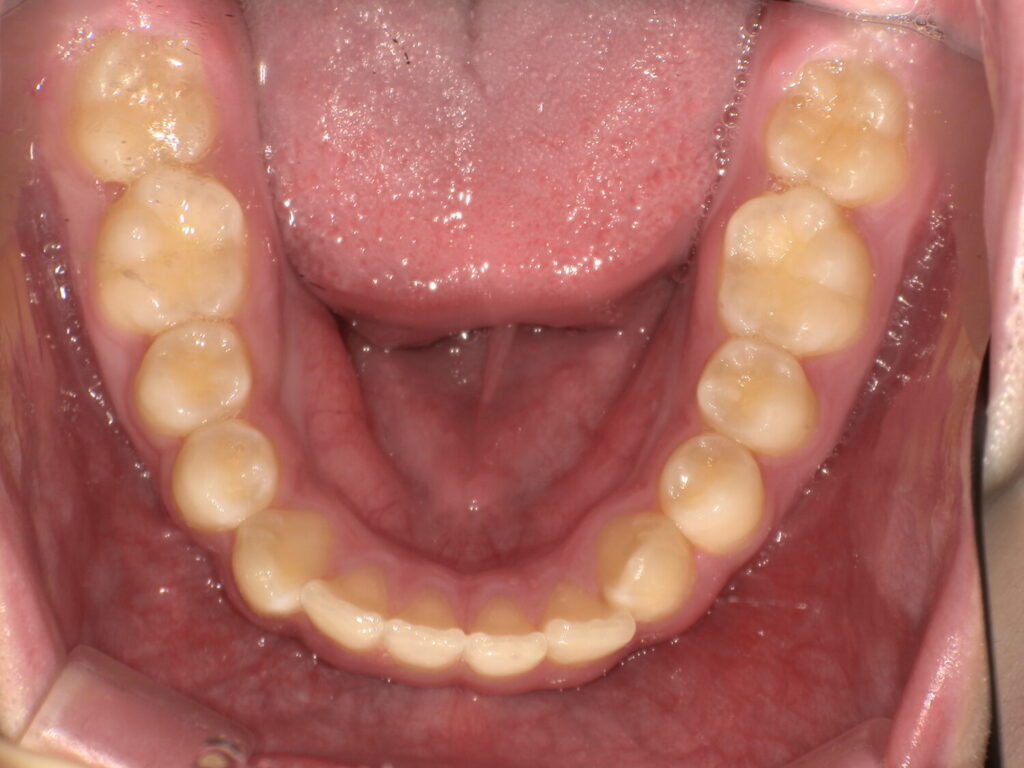

半年後の下の歯の写真です。

がたつきがあったのも綺麗になり、調和の取れた歯並びへ変わってきています!

舌のアクティビティーが少し苦手だったり受験などもあり、3年ほどかかりましたがアクティビティー卒業する頃には綺麗な歯並びになりました!

下の歯もしっかりと見えています。